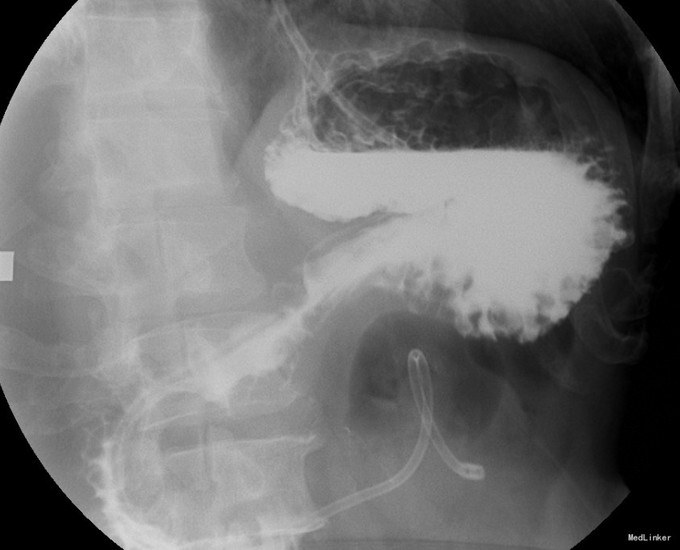

入院后,复查全腹增强CT(图3,图4):结节较前缩小。胃壁增厚。肠癌系列正常。行PET-CT:1、原右肾门水平十二指肠前方FDG高代谢软组织影区域本次扫描代谢未见显著增高,符合治疗后改变。2、右肺上叶多发磨玻璃影,FDG代谢略高,注意重度不典型增生,3、胃窦远端FDG代谢略升高,目前考虑炎症可能大,需密切结合镜下及病理;十二指肠管壁增厚伴周围多发渗出,炎性改变可能大。胃镜:窦前壁近幽门管可见一溃疡性病变,大小约1.5*2.0cm,表面白苔,周围粘膜充血水肿。幽门口变形,收缩舒张不良。十二指肠球部粘膜充血,球后黏膜光滑、色泽正常。此次病理:胃溃疡性病变,局部腺体轻度非典型增生,幽门螺杆菌阴性。上消化道造影(图5):胃窦部变形,胃壁略僵硬。 考虑患者胃窦部病变不能除外恶性。同时肺内病灶不能除外恶性。考虑为肿瘤的复发及远隔转移,手术治疗效果不佳,予以口服化疗药物治疗。空肠营养管建议终身携带,帮助增强营养,如患者不耐受,可以改为内镜下经胃造瘘空肠营养管(PEJ)。随访。